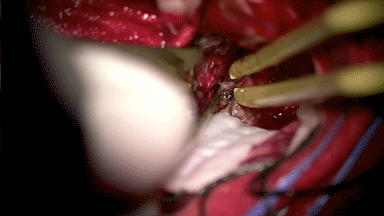

分离海绵窦壁基底

海绵窦壁破损

电凝后使用海绵棉条压迫止血

处理海绵窦硬膜基底其他部分,海绵窦再次出血